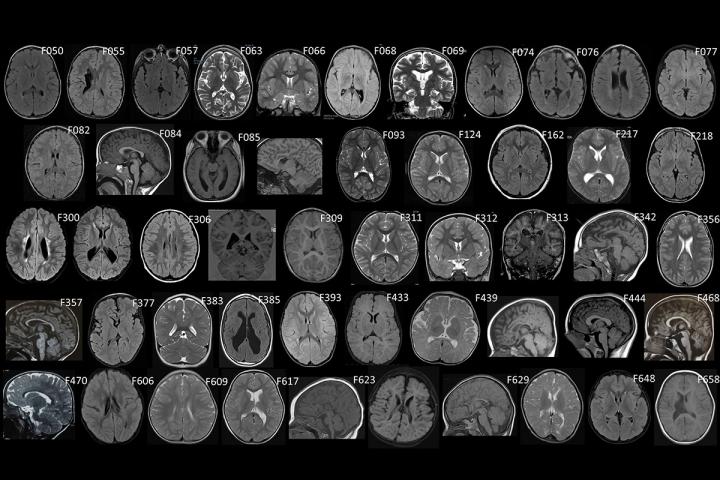

image: Pictured is a set of MRI scans of brains of patients with the neurodevelopmental disorder cerebral palsy. For many patients with the disorder, doctors can't pinpoint the cause. Researchers at Washington University School of Medicine in St. Louis and their colleagues at other institutions have identified mutations in single genes that can be responsible for at least some cases of cerebral palsy.

Kruer Lab